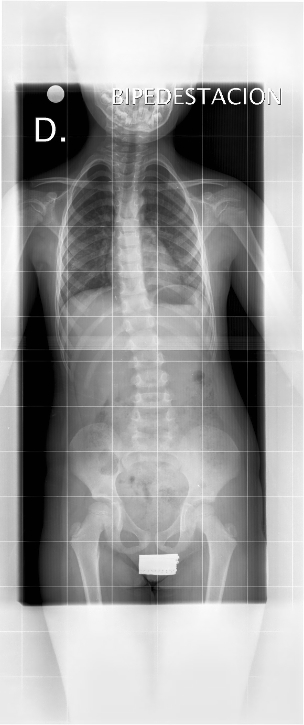

Todo esto explica la repercusión estética (signo de Adams) y pulmonar de la escoliosis. Y esto nada más, define una escoliosis. En la Figura 11 se puede observar una grave escoliosis con una perfecta simetría en los hombros, pelvis y caderas.

Figura 11. Simetría en los hombros pelvis y caderas con una grave escoliosis dorsal. Mostrar/ocultar